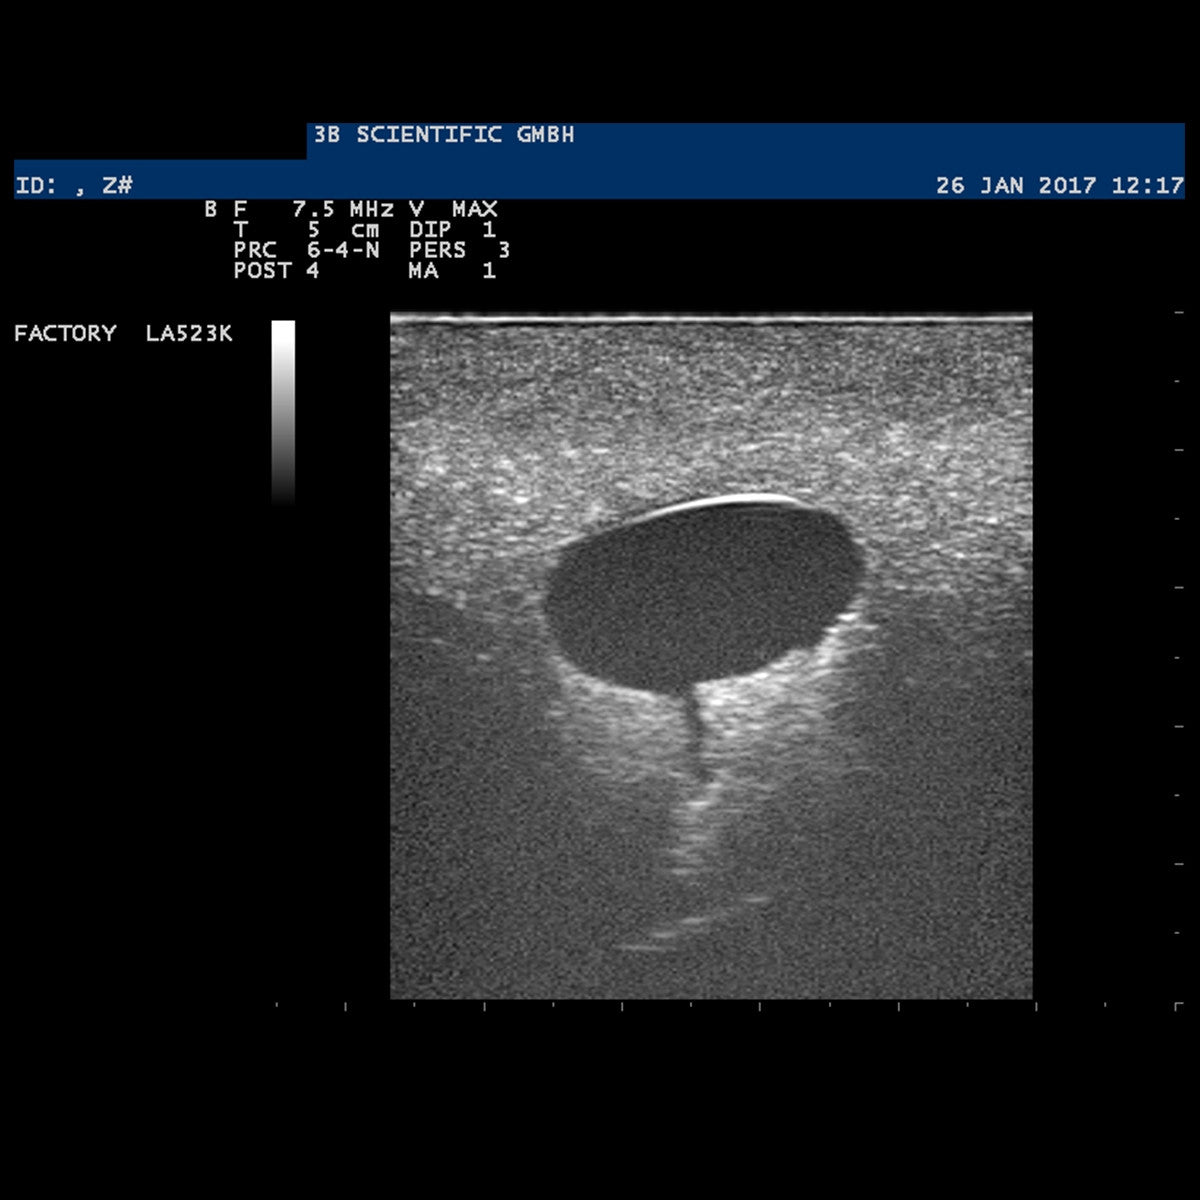

This ultrasound model represents a breast with two cysts to practise aspirations and punctures. This SONOtrain trainer offers soft-feel tissue to enable palpations and injections and has been designed to show texture and echogenicity on ultrasound. This trainer model is cost-effective and easy to use. Available in light and dark skin tone.